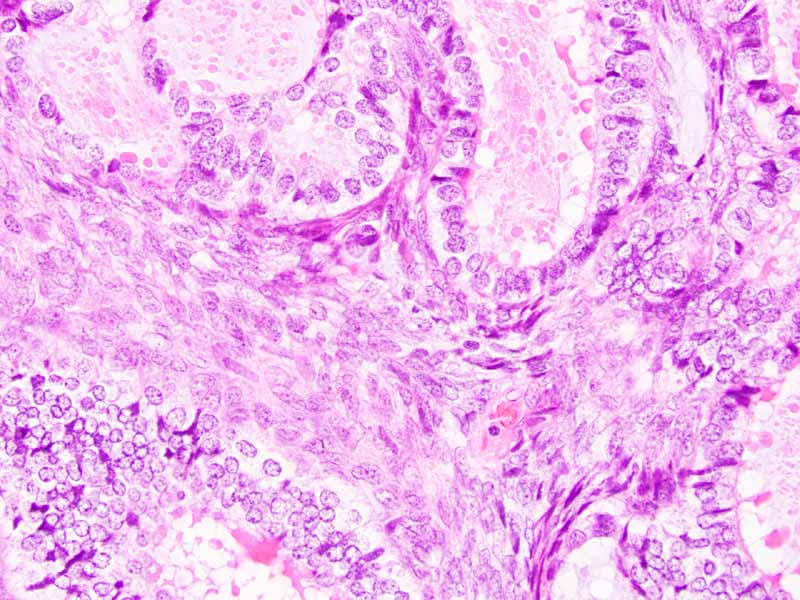

Clinical information: The patient was a 37 year-old woman with a deep 5.5 cm popliteal mass. Based on the FNA finding, the mass was excised and yielded the following images.